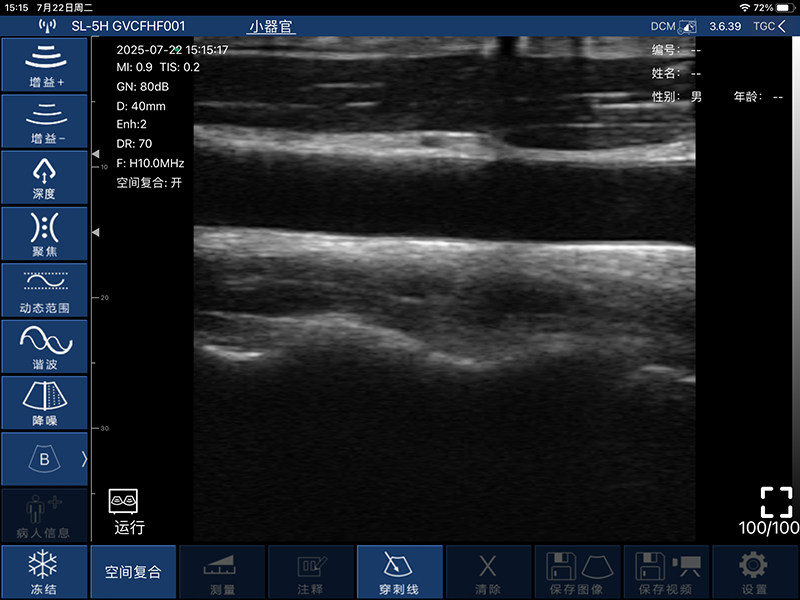

带指套探头的掌上彩超,小小的掌超主机放在口袋可随处走,手指套着探头即可完成打图成像,让手不再需要握着探头而可解放出来还能拿其他东西,特别适合术中等应用

- 扫描方式:电子阵列扫描

- 探头频率:7.5/10MHz

- 扫描宽度:25mm

- 扫描深度:10/20/30/40mm,可调

- 图像调节:增益、焦点、反相脉冲谐波、降噪

- 探头与主机连接方式:wifi无线连接

- 图像帧频:18f/s